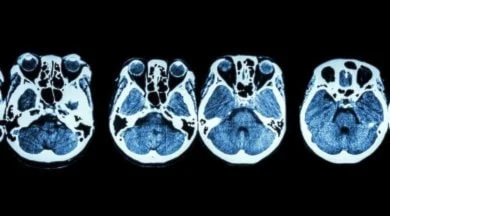

Rinoloji burun ve etrafının her türlü hastalığını ve cerrahi tedavisini konu alan bilim dalıdır. Temelde yüz, sinüsler ve burnun her türlü hastalığı rinolojinin konusudur. Rinoloji ve kafa tabanı cerrahisi KBB hastalıklarının özel bir alanıdır. Burun boşluğunun ve bazı sinüslerin tavanı içinde beynin yerleşmiş olduğu kafatasının tabanını yani kafa tabanını oluşturur. Kafa tabanı cerrahisi hem kanserli olmayan hem de kanserli büyümeleri ve beynin alt kısmındaki, kafa tabanındaki veya omurganın üst birkaç omurlarındaki anormallikleri gidermek için yapılabilir. Bu bölge, görülmesi ve ulaşılması oldukça zor bir alandır. Bilgisayarlı Tomografi (BT) veya Manyetik Rezonans görüntüleme (MR) teknikleri bu anormallikler yüksek derecede doğrulukla tespit edebilmektedir.